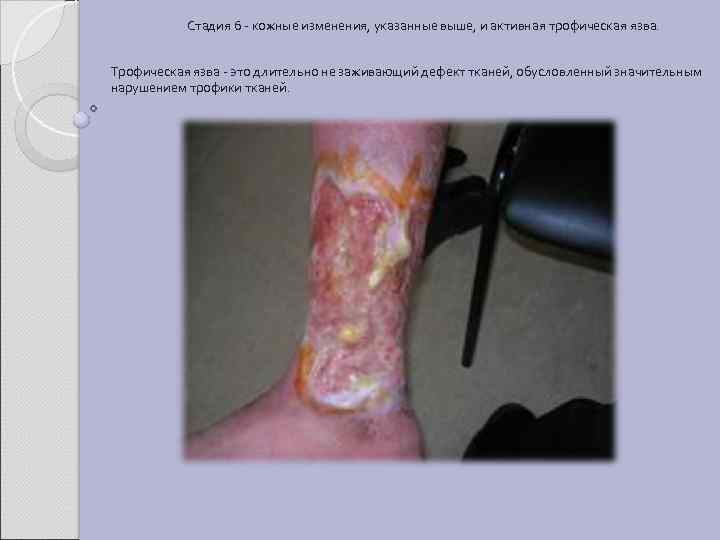

Стадия 6 - кожные изменения, указанные выше, и активная трофическая язва. Трофическая язва - это длительно не заживающий дефект тканей, обусловленный значительным нарушением трофики тканей.